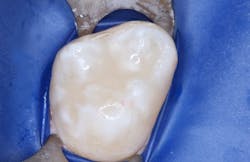

- Place sealant/flowable resin and cure (figure 4).